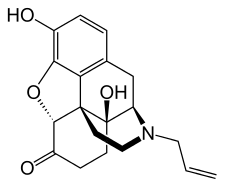

Several semi-synthetic opioids were developed in Germany in the 1910s. The first, oxymorphone, was synthesized from thebaine, an opioid alkaloid in opium poppies, in 1914.[228] Next, Martin Freund and Edmund Speyer developed oxycodone, also from thebaine, at the University of Frankfurt in 1916.[229] In 1920, hydrocodone was prepared by Carl Mannich and Helene Löwenheim, deriving it from codeine. In 1924, hydromorphone was synthesized by adding hydrogen to morphine. Etorphine was synthesized in 1960, from the oripavine in opium poppy straw. Buprenorphine was discovered in 1972.[228]